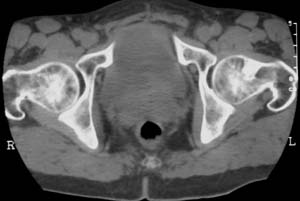

男,61岁,左侧髋关节疼痛,负重后更明显

现上传ct片

左侧股骨头增密,其内见有囊变密度减低区,关节面骨质硬化,关节间隙及髋臼无异示。考虑股骨头缺血坏死可能。建议mri检查。

我觉得股骨头未见到明显的问题,左侧股骨颈有卵圆形高密度影,考虑骨岛或骨梗死。

1\\左侧股骨颈有卵圆形高密度影,考虑骨岛或骨梗死。2\\由于临床症状疼痛,应该mri检查排除早期股骨头缺血坏死

左侧股骨颈处一卵圆形密度增高影,边界清,临近骨组织未见明显破坏.考虑为骨梗死,骨岛?